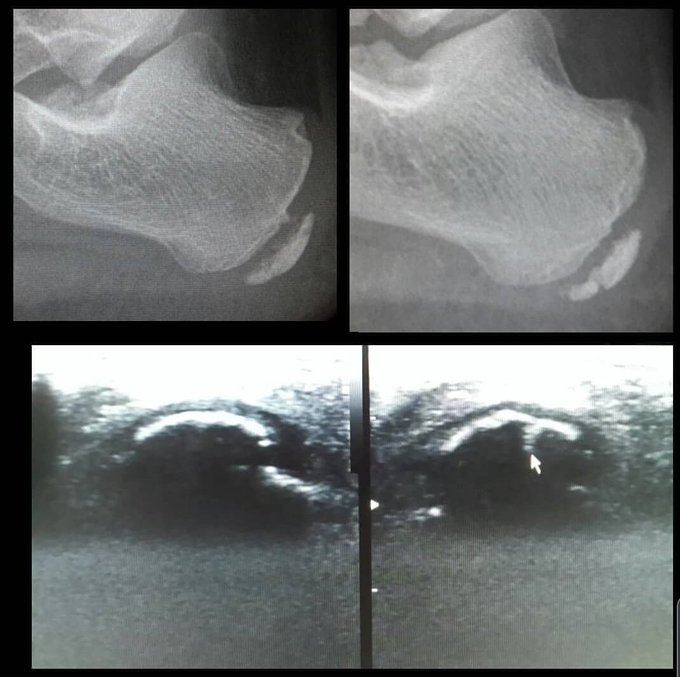

@WYIAnX4oUlPPqr5 @drmariochavez Fractura del cartílago de crecimiento por trauma deportivo (Atletismo)